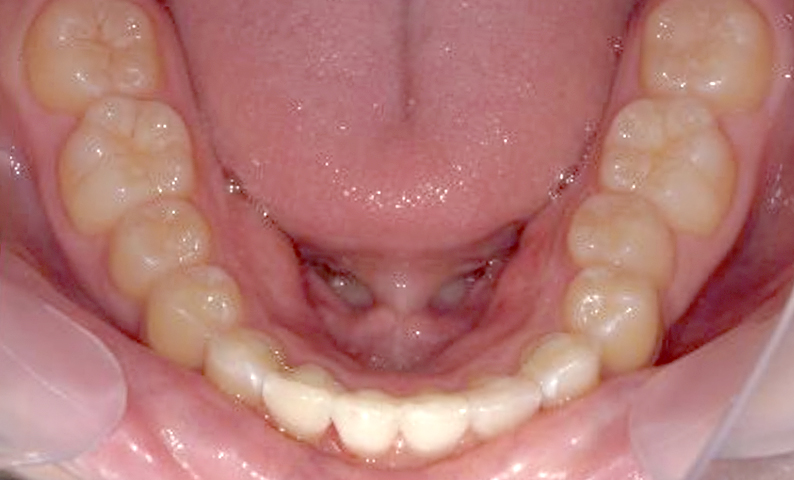

症例_001 前歯「捻転歯」症例

治療期間:6ヶ月金額:48万円+税20代女性少しのねじれ捻転歯下の八重歯

| Before | After |